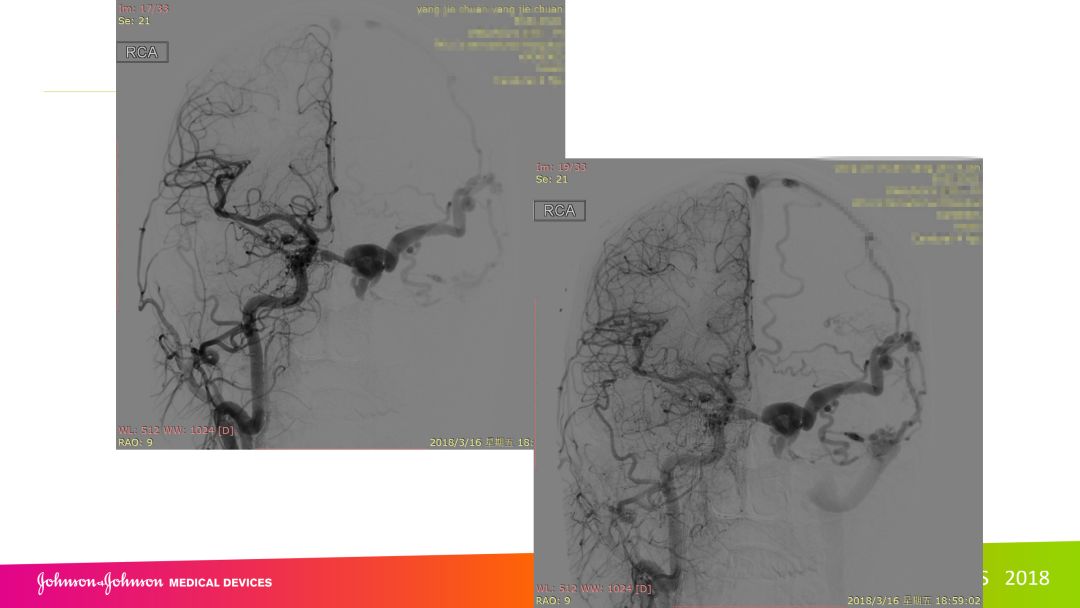

复合手术治疗海绵窦区硬脑膜动静脉瘘一例